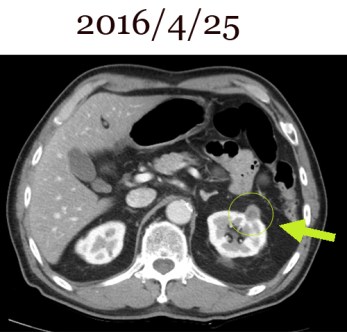

1-3.jpg

이 환자는 당시 1년 이상 치료를 한 후에 골반벽과 복부에 있는 임파절이 다 없어졌고 폐에도 multiple 하게 보이던 종양이 소실되었고 위에 사진에 보듯이 우측 하엽에 보이던 종양도 소실이 되어서 전립선암 완치 판정을 받았다. 이전 CT가 여러 군데 흩어져 잘 찾아지지 않아서, 여기서는 2016년도 신세포암을 발견하고 가져왔던 사진으로 비교를 해 본다. 위의 사진(2016/4/25)을 보면 전립선의 크기도 현저히 줄어들었다. 이전의 골반벽림프절들은 모두 소실이 되었다.

정영기1-5.jpg

이분은 2014년 한약을 중단하고 나서  1년 지나서 위장에 매우 초기 종양이 발견되어서 수술로 제거하고, 방사선이나 약물치료 없이 추적관찰 중이었는데  2016년도에 또다시 신장에 신세포암이 발생하였다.  2014년 이후에는 본원의  치료를 받지 않았지만 위암은 무사히 지나갔고,  2016년 4월 사진에서 좌측 신장에 작은 암이 발견되어서 복강경으로 제거를 하였다.

1-5.jpg

환자는 전립선암은 마쳤지만 다시 위암이 발생하고  또 위암은 끝났는데 연이어 신세포암이 발생하여서 아직 투병이 끝나지 않은 상태에서  2017년도 3월에 CT를 가지고 찾아왔다. 이전에 전립선암 때 한때 다 사라져서 보이지 않았지만 , 2017년 C 에서는 매우 미세한 nodule들이 폐에 몇 개 보였는데, 나름대로 생각이 있어서 그런지 한방치료를 택하지는 않았다. 이 신장에 보이는 작은 종양은 위에서 보듯이  2016/4/25일 검사에서 신세포암일 가능성을 시사하였고, 위벽이나 위 혹은 복부에 다른 임파절은 없다는 설명이다. 이전 전립선암 때 열거되었던 수많은 복부와 골반벽임파는 다 소실이 되었고  폐에 위의 사진에서 보듯이 작은 점이 하나 남아있는데, 이는 양성인 granuloma로 보인다는게 아산병원의 그간 추적의 소견이다. 이 환자도 중간 과정을 CT를 찾아보니 다른 콤퓨터에 흩어져 있어서 바로 1년 뒤에 소실되었을 때를 비교해서 시를 못한다. 그래서 2016년도 복부사진을 통해서 초기 2010년 사진과 비교해 보았다. 이를 보면 이전 종양들은 다 사라진 것을 알 수 있을 것이다.